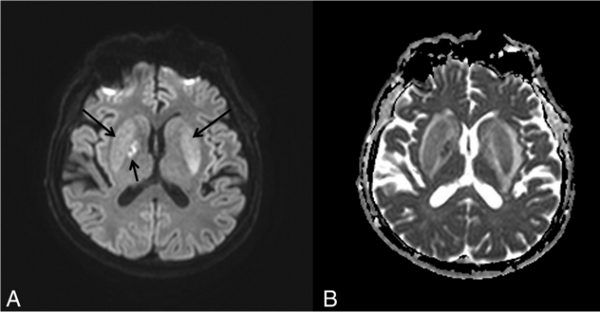

На Т2-WI (А) и схеме (В) отображены изменения, имеющие внешнее сходство с вилкой. Яркий гиперинтенсивный ободок очерчивает латеральную (наружная капсула, длинная стрелка) и медиальную (латеральная мозговая пластинка, короткая стрелка и медиальная мозговая пластинка, тонкая стрелка) границы скорлупы с обеих сторон. Бледный шар разделен на 2 части медиальной мозговой пластинкой, которая видна на МРТ при патологических состояниях. FLAIR-изображение (С) иллюстрирует мультифокальные относительно симметричные извилины с высоким сигналом (стрелки) в коре лобной и теменно-затылочной долей, а также в базальных ганглиях билатерально.

DWI-изображение (А) и ADC-карта (В) иллюстрируют незначительное повышение сигнала (длинные стрелки) в базальных ганглиях билатерально и фокальное ограничение диффузии (короткая стрелка), что является следствием цитотоксического отека в правом базальном ганглии.